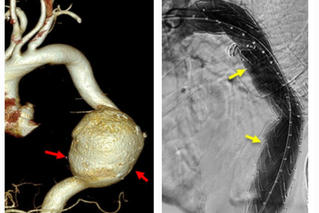

từ khóa: #vỡ phình động mạch chủ